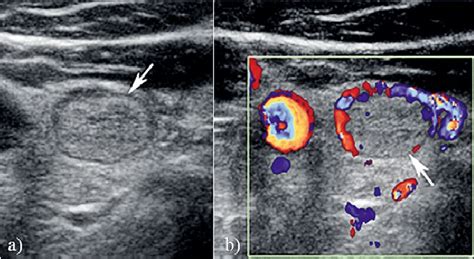

Isoechoic nodule with hypoechoic rim.  2: Isoechoic nodule within the ...Isoechoic nodule with hypoechoic rim.  2: Isoechoic nodule within the ...